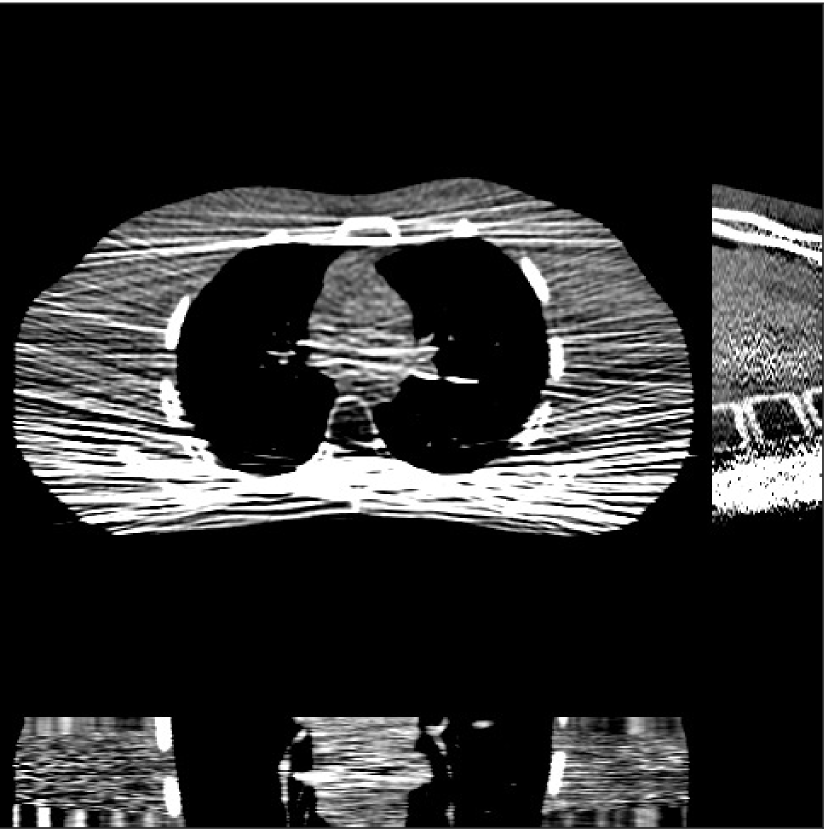

Fig. 4 shows the reconstructed images and the corresponding error images for PWLS-EP, PWLS-ULTRA, and SPULTRA, at and . Compared to the PWLS-EP result, both PWLS-ULTRA and SPULTRA achieved significant improvements in image quality in terms of sharper reconstructions of anatomical structures such as bones and soft tissues, and suppressing the noise. However, the PWLS-ULTRA method introduces bias in the reconstructions, which leads to larger reconstruction errors compared to the proposed SPULTRA method. In Fig. 4, we marked three 3D ROIs in the axial plane, i.e., ROI 1, ROI 2, and ROI 3. Fig. 5 shows the zoom-in images of a 3D plot of ROI 1, and those of ROI 2 and ROI 3 are shown in the supplement. We also plot the evolution of RMSE through the axial slices of the three 3D ROIs in Fig. 6. The figures demonstrate that SPULTRA clearly outperforms the competing PWLS-EP and PWLS-ULTRA schemes.

The above advantages of SPULTRA can be seen more clearly when observing the image profiles. Fig. 7 plots the image profiles for the three methods together with that of the ground-truth image. Fig. 4 shows the horizontal green solid line and the vertical red dashed line, whose intensities are plotted in Fig. 7. It is obvious that the profiles for SPULTRA are closest to the ground-truth among the three compared methods. The gap between the profiles of the PWLS-based methods and the ground-truth shows the bias caused by the compared PWLS methods.

Fig. 9 shows three axial slices from the 3D reconstructions with SPULTRA and PWLS-ULTRA at : the middle slice (No. 67) and two slices located farther away from the center (No. 90 and No. 120). The image profiles along a horizontal line (shown in green) in the displayed slices are also shown in Fig. 9. The reconstructed slices using PWLS-ULTRA appear darker around the center compared to the “true” clinical image and the reconstructions with SPULTRA. This means PWLS-ULTRA produces a strong bias in the reconstruction. The bias can be observed more clearly in the profile plots: the pixel intensities for the SPULTRA reconstruction better follow those of the “true” clinical image, while those for the PWLS-ULTRA reconstruction are much worse than the “true” values. Moreover, SPULTRA achieves sharper rising and failing edges compared to PWLS-ULTRA. In other words, SPULTRA also achieves better resolution than PWLS-ULTRA. Fig. 9 also shows a zoomed-in ROI for each of the chosen slices, and highlights some small details with arrows. It is clear that in addition to reducing the bias, SPULTRA reconstructs image details better than PWLS-ULTRA.